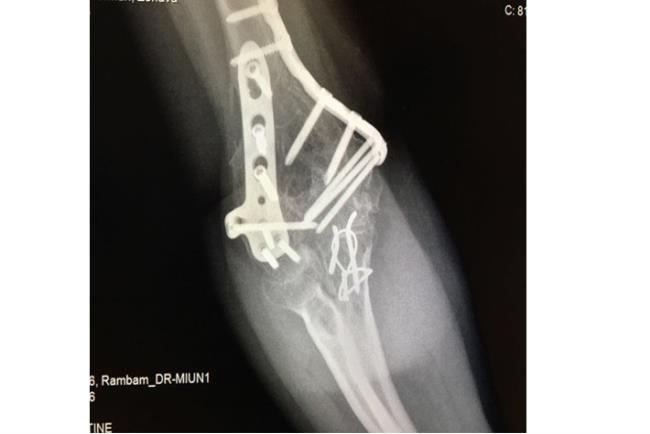

בשלב הראשון יתבצע צילום רנטגן. אם עולה חשד לכך שהשבר מערב גם את המפרק תתבצע גם בדיקת CT לשם הדמיה תלת ממדית של האזור הפגוע וחלקי השבר אותם יש להרכיב כדי להשיב למפרק את תנועתו התקינה. לרוב, כדי לטפל בשברים מורכבים יתבצע ניתוח ולא קיבוע בגבס.מטרת הטיפול בגבס היא קיבוע המצב הקיים ועל כן במקרה של שבר מורכב טיפול זה לא יועיל בהשבת התפקוד המפרקי. לכן, כדי להשיב את המצב לקדמותו יש צורך בפתיחת המפרק, העמדת כל אחד מחלקי העצם במקומו וחיבור החלקים אחד אל השני. הניתוח והקיבוע נעשים ע"י פלטות ברגים ומסמרים תוך לשדיים העשויים טיטניום או סוג של פלדת אל חלד.

קיבוע פנימי של המרפק | באדיבות פרופ' דורון נורמן